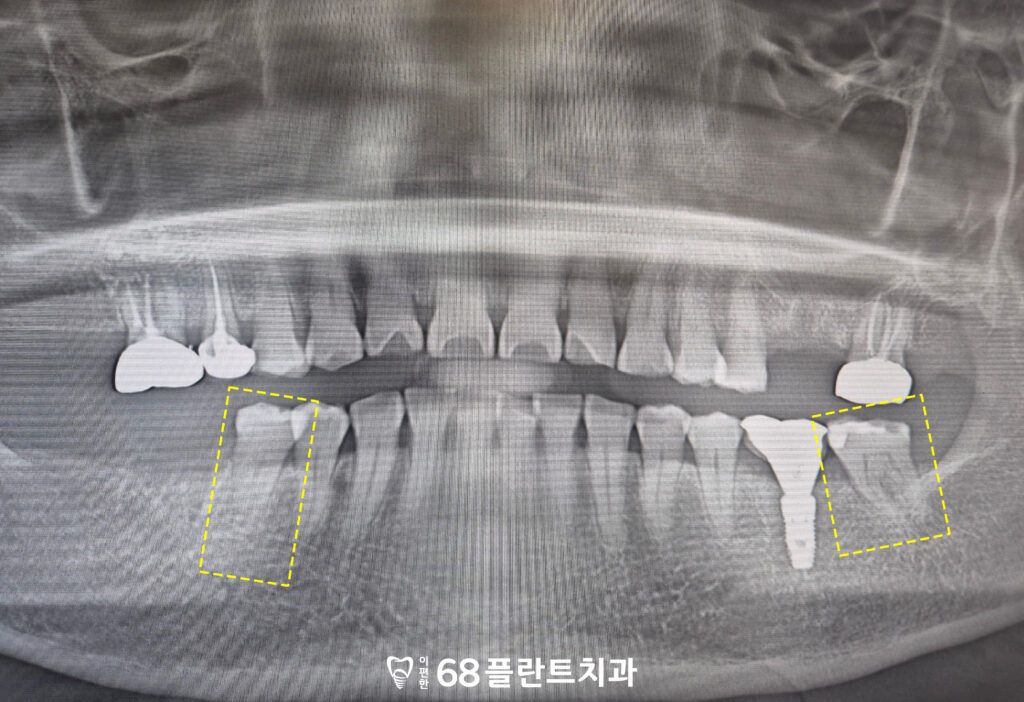

아래 두 치아는

크랙과 함께 교모가 진행된 상태였지만,

다른 치아들에 비해 통증이 크지 않고

치아 뿌리와 주변 조직 상태가

비교적 안정적이었습니다.

이에 본원에서는

치아를 보존하는 방향으로

치료 계획을 세워

살려서 사용해보기로 하였습니다.

치료 과정 중 통증이나

증상 변화가 나타날 경우를 대비해

상황에 따라 신경치료를 병행하기로 하고,

이후 크라운 치료를 통해

저작 기능과 치아 보호를 함께

도모할 예정이었습니다.